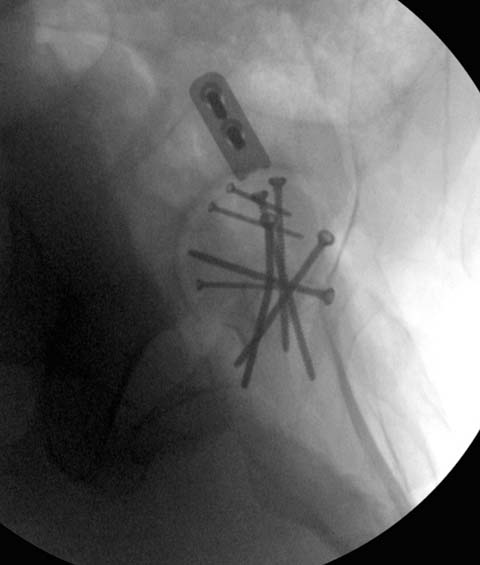

Здесь клинические примеры: Первый случай передний доступ, второй с ICP

monitor Flipp Trochanteris

и с переломом заднего края.